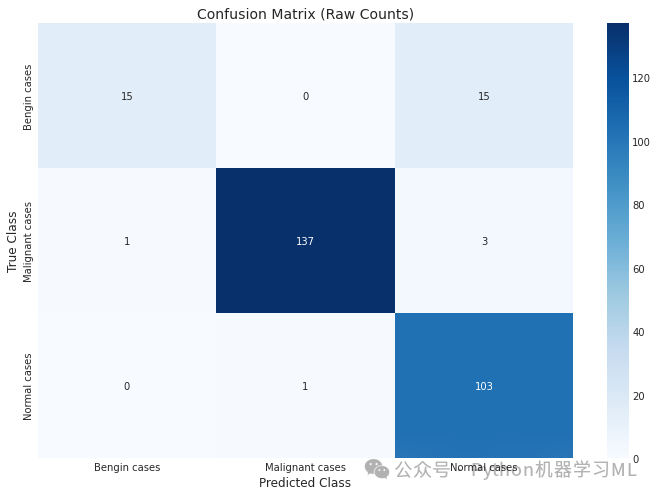

Classification Report:[[ 15 0 15] [ 1 137 3] [ 0 1 103]]Classification Report: precision recall f1-score support 0 0.94 0.50 0.65 30 1 0.99 0.97 0.98 141 2 0.85 0.99 0.92 104 accuracy 0.93 275 macro avg 0.93 0.82 0.85 275weighted avg 0.93 0.93 0.92 275

第二阶段:混淆矩阵可视化

python# 2. Enhanced confusion matrix visualization

plt.figure(figsize=(10, 8))

conf_mat_norm = conf_mat.astype('float') / conf_mat.sum(axis=1)[:, np.newaxis] # 计算归一化的混淆矩阵

# Plot original confusion matrix

plt.figure(figsize=(12, 8)) # 创建新图形

sns.heatmap(conf_mat, annot=True, fmt='d', cmap='Blues',

xticklabels=categories,

yticklabels=categories) # 使用热力图绘制原始混淆矩阵

plt.xlabel('Predicted Class') # 设置x轴标签

plt.ylabel('True Class') # 设置y轴标签

plt.title('Confusion Matrix (Raw Counts)') # 设置标题

plt.savefig("Confusion Matrix (Raw Counts)") # 保存图形

plt.show() # 显示图形